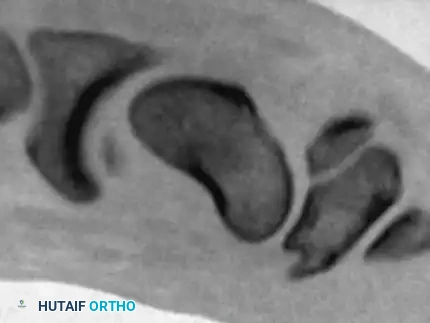

Computed Tomography (CT) is the gold standard for evaluating scaphoid nonunions, assessing the extent of osteolysis, and quantifying the humpback deformity. Because the scaphoid lies obliquely within the carpus (flexed approximately 45 degrees to the longitudinal axis of the radius), standard orthogonal CT planes of the wrist do not provide true anatomical cross-sections of the scaphoid.

To accurately assess the intrascaphoid angle and plan for structural grafting, CT images must be reformatted along the true longitudinal and short axes of the scaphoid.

Images obtained in this specialized sagittal plane are optimal for measuring the intrascaphoid angle and quantifying the degree of volar flexion (humpback deformity) of the distal pole relative to the proximal pole.

Coronal Plane Imaging:

Interpretation of images obtained in this true coronal plane is straightforward, allowing for precise evaluation of the fracture gap, cyst formation, and the integrity of the proximal pole articular surface.